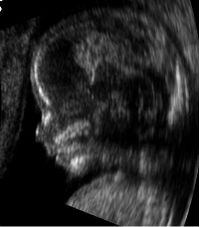

- متابعة وتصوير الجنين أثناء فترة الحمل.

| طب التوليد | Obstetrical sonography is commonly used during pregnancy to check on the development of the fetus. | انظر obstetric ultrasonography |

صورة ثلاثية الأبعاد لجنين عمره 29 أسبوع.